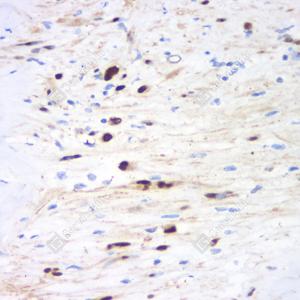

IHC检测S100 beta蛋白(货号 GB12360). 样品: 人外周神经鞘瘤, 4%多聚甲醛 (货号G1101) 固定12-24小时. 抗原修复: 柠檬酸抗原修复液(干粉, pH 6.0) (G1201), 98℃, 20分钟. —抗: 1: 1000稀释, 4℃ 孵育过夜. 二抗: HRP标记山羊抗小鼠IgG (H+L) (货号GB23301), 1: 200稀释, 室温孵育1小时. |

IHC检测S100 beta蛋白(货号 GB12360). 样品: 小鼠脑, 4%多聚甲醛 (货号G1101) 固定12-24小时. 抗原修复: 柠檬酸抗原修复液(干粉, pH 6.0) (G1201), 98℃, 20分钟. —抗: 1: 1000稀释, 4℃ 孵育过夜. 二抗: HRP标记山羊抗小鼠IgG (H+L) (货号GB23301), 1: 200稀释, 室温孵育1小时. |

IHC检测S100 beta蛋白(货号 GB12360). 样品: 大鼠脑, 4%多聚甲醛 (货号G1101) 固定12-24小时. 抗原修复: 柠檬酸抗原修复液(干粉, pH 6.0) (G1201), 98℃, 20分钟. —抗: 1: 1000稀释, 4℃ 孵育过夜. 二抗: HRP标记山羊抗小鼠IgG (H+L) (货号GB23301), 1: 200稀释, 室温孵育1小时. |